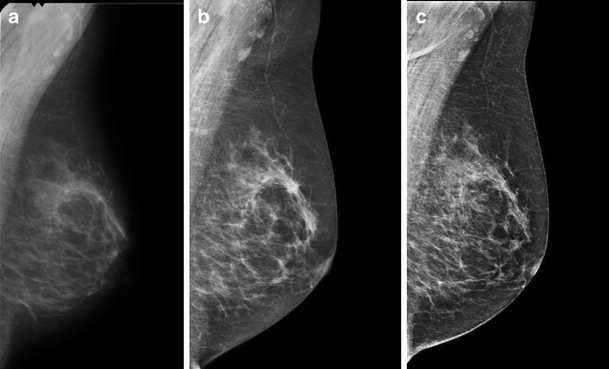

Pseudolesion seen with high contrast resolution in FFDM. a Prior screening mammogram (SFM), b screening mammogram followed by referral (FFDM), c mammogram in subsequent clinical assessment (FFDM)

Secondly, higher contrast resolution improves the detection of microcalcifications [14]. This explains the increased share of referrals on the basis of microcalcifications and is in line with the significant increased detection of ductal carcinoma (both in situ and invasive) found in our previous study [11]. Since most clusters of microcalcifications do not represent malignancy, interpreting calcification type is another challenge in FFDM. Therefore, it is not surprising that in the first few months of digital screening we have seen an exceedingly high proportion of false-positive referrals due to microcalcifications.

The superior contrast resolution of digital mammography had yet a third effect. Compared with a previous conventional image, a digital mammogram can falsely give the impression that a lesion or cluster of microcalcifications is new or has grown. This doubt about progression in the presence of conventional prior mammograms can cause more women to be referred. While in other studies prior mammograms were offered only on request [5] or not until consensus meeting [4], we had (digitised) prior mammograms present at all times. Prior mammograms increase the specificity of screening [15] and not presenting them instantaneously was considered unethical. Accordingly, the introduction of subsequent screens a few months after the pilot started resulted in a second rise in referral.